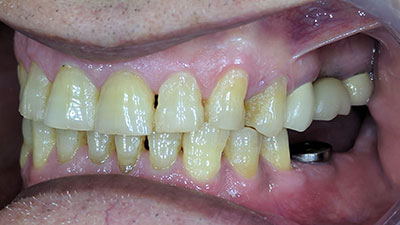

Introduction Successfully treating patients with missing or non-restorable teeth with a fixed prosthesis can be one of the finest services rendered to dental patients. This art and science of replacing missing teeth or those with hopeless prognosis requires a thoughtful combination of many aspects of dentistry, including patient education, prevention of further dental disease, sound … Read more